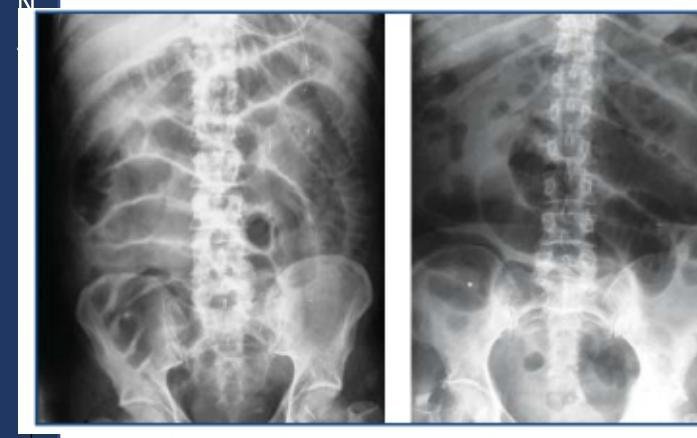

# OCLUSIÓN INTESTINAL ## DEFINICIÓN Se define como la **INTERRUPCIÓN DEL TRÁNSITO INTESTINAL**, lo que impide expulsar gases y heces por el recto. El bloqueo de la luz intestinal se da en su mayoría por factores extrínsecos (adherencias, hernia inguinal, hernia de pared estrangulada) y en pocas ocasiones por obstrucción de la luz. **ADHERENCIAS PERITONEALES**: son bandas fibrosas entre órganos o tejidos o ambos en la cavidad abdominal que normalmente están separados. TIPOS DE ÍLEO | PARALÍTICO / ADINÁMICO | Existe una causa funcional que altera el peristaltismo. La causa más frecuente es la cirugía abdominal (íleo reflejo postquirúrgico). Tras la cirugía, el intestino delgado es el primero en recuperar la movilidad a las 24 horas, seguido del estómago 48 horas, el colon tarda 3 -5 días. | | :--: | :-- | | OBSTRUCTIVO / MECÁNICO | Existe una causa orgánica que lo produce como son las barreras físicas que obstruyen la luz. | | ESPÁSTICO | Hiperactividad descoordinada del intestino que se observa en la intoxicación por metales pesados, porfiria y uremia. Se debe tratar la enfermedad sistémica. | | ÍLEO DE LA OCLUSIÓN VASCULAR | Movilidad descoordinada del intestino isquémico | ## EPIDEMIOLOGÍA - LAS **ADHERENCIAS SON LA CAUSA MÁS COMÚN DE OCLUSIÓN INTESTINAL** - Responsables en 65 - 75 % de los casos (mortalidad de 3.5 - 6%) - El 70% de las adherencias responde a manejo conservador, un 30% requiere manejo quirúrgico. - En el intestino delgado, la obstrucción mecánica es el trastorno quirúrgico más frecuente. ## FACTORES DE RIESGO - Adherencias - **Hernia inguinal** (primera causa en pacientes sin cirugía previa) - **Hernia de pared estrangulada** - Neoplasias - Íleo por cálculo biliar - **Enfermedad de Crohn** - **Vólvulo** - **Intususcepción** - Divertículo de Meckel - **Cuerpo Extraño** # CLÍNICA - **DOLOR ABDOMINAL TIPO CÓLICO** + **NÁUSEA**, **VÓMITO** Y **ESTREÑIMIENTO** - El vómito es más prominente en las obstrucciones proximales - La distensión se asocia al íleon distal. - Los ruidos intestinales son hiperactivos al principio, luego son mínimos | INTESTINO DELGADO | Dolor abdominal, vómitos (fecaloides si es distal), distensión abdominal, hiperperistaltismo con ruidos metálicos | | :--: | :--: | | INTESTINO GRUESO | Dolor y distensión abdominal Vómitos y estreñimiento Incapacidad de expulsar gases y heces | **Obstrucción Estrangulada**: Dolor abdominal desproporcionado, taquicardia, fiebre, leucocitosis y acidosis. ## DIAGNÓSTICO **GOLD STANDARD: RADIOGRAFÍA DE ABDOMEN** (En decúbito y de pie) + Tele de Tórax de pie. ## TRIADA DE RX: - Asas en Intestino delgado dilatadas (+3 cm de diámetro) - Niveles hidroaéreos - Escasez de aire en el colon  Radiografía en decúbito con dilatación de asas de intestino delgado con válvulas conniventes (separado de la base y por el extremo en contacto)  Signo de Collar de Perlas: representa pequeñas cantidades de aire atrapado en las válvulas del intestino delgado, predominantemente lleno de líquido. Se presenta en obstrucción mecánica de ID. DATOS EN **TAC**: 1. Dilatación proximal del intestino 2. Descompresión distal del intestino 3. Contraste luminal que no pasa más allá de la zona de transición 4. Colon con poco gas o líquido 5. Signo de las heces (burbujas)   Signo de **PILAS DE MONEDAS**: Pliegues intestinales engrosados, lisos, rectos y perpendiculares al eje longitudinal de la luz. # TRATAMIENTO ## CONSERVADOR ## SONDA NASOGÁSTRICA / TUBO INTESTINAL LARGO - El 90% de las obstrucciones de ID se resuelven con **SNG y REPOSICIÓN HIDROELECTROLÍTICA** - Debe mantenerse durante 48 - 72 horas. - Si existe obstrucción por estrangulación, obstrucción maligna, hernias encarceladas, cuerpo extraño, enteritis por radiación, peritonitis o abdomen agudo, debe considerarse **cirugía**. ## QUIRÚRGICO Deberá considerarse el manejo invasivo en los siguientes casos: A. **Íleo mecánico intestinal por más de 3 días** B. Drenaje por SNG al tercer día >500 ml C. Edad menor a 40 años o adherencias complejas D. **Obstrucción completa** del intestino delgado (sin aire en intestino grueso) y CPK mayor a 130 Considerar **Cirugía INMEDIATA** en los siguientes casos: - Cirugía dentro de las 6 semanas previas al cuadro de oclusión - Cuadro no resuelto con manejo conservador en las 48-72 horas a pesar de utilizar medio de contraste hidrosoluble por SNG - Presencia de líquido intraperitoneal, edema del mesenterio y signo de las heces en intestino delgado - Dolor abdominal mayor a 4, resistencia abdominal, leucocitos 10,000 o más, PCR 75 mg - Datos de **estrangulación**: fiebre, taquicardia, leucocitosis, acidosis metabólica. ## LAPAROTOMÍA EXPLORADORA 1. La incisión debe permitir tener una adecuada exposición y visibilidad 2. Identificar sitio y causa de obstrucción, si no es obvio, hay que descomprimir el intestino hasta encontrarla 3. Si el intestino está isquémico hay riesgo de ruptura con salida de contenido a cavidad abdominal 4. Después de corregir obstrucción se deben explorar los cuatro cuadrantes. 5. Si es requerido, realizar resección intestinal y anastomosis primaria. ## LAPAROSCOPÍA Solo se realizará en un grupo selecto de pacientes como abordaje - Casos de un primer episodio de oclusión intestinal por **adherencias** - Diámetro intestinal menor a 4 cm . - Sospecha de una banda - Antecedente de 2 o menos laparotomías - Antecedente de apendicectomía o colecistectomía puede someterse a laparoscopía. # ANEXOS